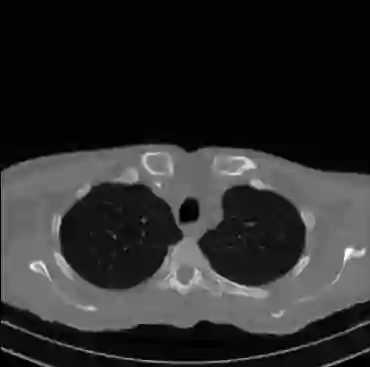

Early and reliable COVID-19 diagnosis based on chest 3-D CT scans can assist medical specialists in vital circumstances. Deep learning methodologies constitute a main approach for chest CT scan analysis and disease prediction. However, large annotated databases are necessary for developing deep learning models that are able to provide COVID-19 diagnosis across various medical environments in different countries. Due to privacy issues, publicly available COVID-19 CT datasets are highly difficult to obtain, which hinders the research and development of AI-enabled diagnosis methods of COVID-19 based on CT scans. In this paper we present the COV19-CT-DB database which is annotated for COVID-19, consisting of about 5,000 3-D CT scans, We have split the database in training, validation and test datasets. The former two datasets can be used for training and validation of machine learning models, while the latter will be used for evaluation of the developed models. We also present a deep learning approach, based on a CNN-RNN network and report its performance on the COVID19-CT-DB database.